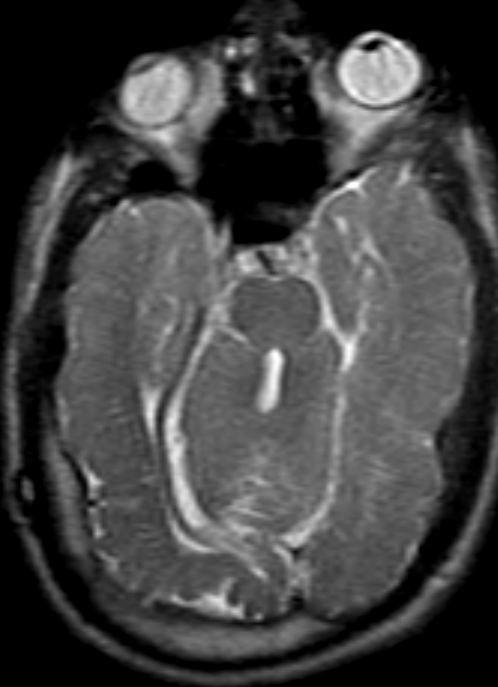

Malrotated hypoplastic vermis, with vertical primary fissure.

“OPEN” fastigial point of the fourth ventricle. Hypoplastic cerebellar hemispheres.

Enlarged posterior fossa

Cystic dilatation 4th ventricle

Uplifted tentorium, TSV sinus, torcula

“torcula-lambdoid inversion” with torcula above the lambdoid suture

Agenetic or hypogenetic vermis with “vermian tail, pushed upward

Cerebellar hypoplasia

CC anomalies 32%

Hydrocephalus up to 90%

Aqueductal stenosis

4th ventricle outlet obstruction

Polymicrogyria, heteropia 5-10%

Occipital Meningo-Encephaloceles 16%

Syndromic = Extracranial anomalies 50%